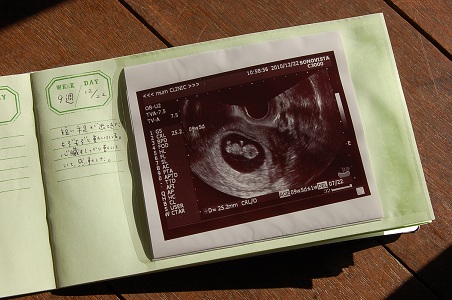

エコー写真

先日旦那さんと産院に行ってきた。

一緒に診察室に入って、エコーで子宮内の様子も見た。

前回は1.2cmの丸く白い影だったのに、たった二週間で2.5cmの2頭身に。

しかも短い手足が出てきていて、まるでテディベアみたいだった。

その短い手足でもぞもぞと動く姿は何とも可愛らしく、愛おしかった。

今9週で、出産予定日は7月22日だそう。